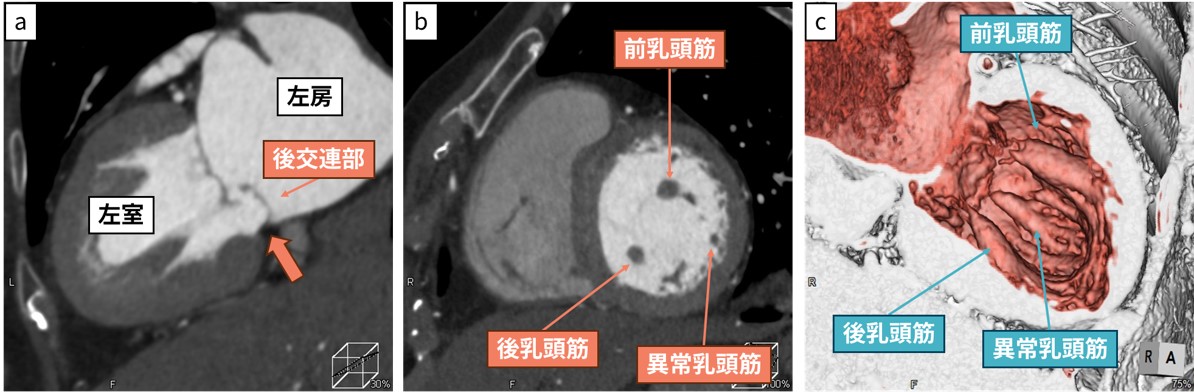

図3 異常乳頭筋を伴う僧帽弁逸脱症症例

a: 二腔断像

b: 左室短軸像

後交連部には逸脱と5㎜のmitral annular disjunctionを認める。

前・後乳頭筋の間に低形成の異常な乳頭筋を認める。